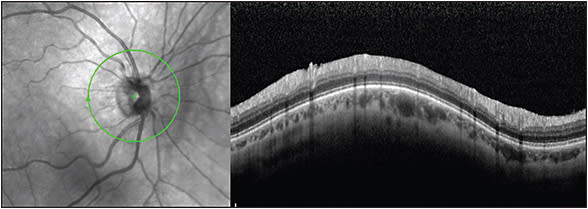

One of the very commonly used modules of OCT can be very useful in unequivocally and very reliably (approximately 95% specificity and sensitivity, based on the author’s experience) demonstrating a PVD. The nerve fiber layer (NFL) module of the OCT (Heidelberg or Zeiss) often demonstrates a line above the retina. This, in the author’s opinion, represents posterior hyaloid still attached to the ONH (Figures 1 and 2). Note the faint nature of the reflection in Figure 1A. Most of the time, however, the line is much more defined and much more easily visualized, as in Figure 1B. This easy use of an already existing module on all OCT machines has proven to be very reliable and has helped us advise patients more accurately, especially when a Weiss ring is not visualized.

A 56-year-old patient presented with new floaters in both eyes. The exam was difficult, and a Weiss ring could not be visualized in either eye. The OCT imaging showed PVD in the right eye (Figure 3) but not in left (Figure 4), which meant that the lack of a Weiss ring visualization was due to the exam difficulty in the right eye while in the left eye it was because the vitreous was not yet completely separated. The patient was advised accordingly.